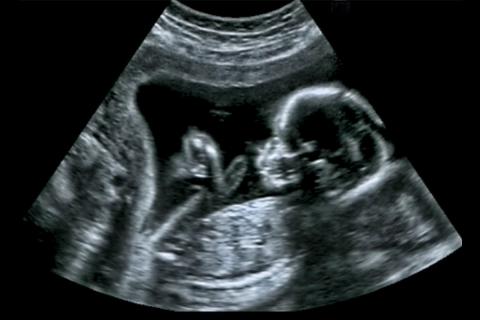

Draper’s initial concept is an ultrasound blanket or similarly flexible material that can be draped easily over a mother’s abdomen, requiring no specific orientation or alignment by the operator. (Credit: Shutterstock.com)